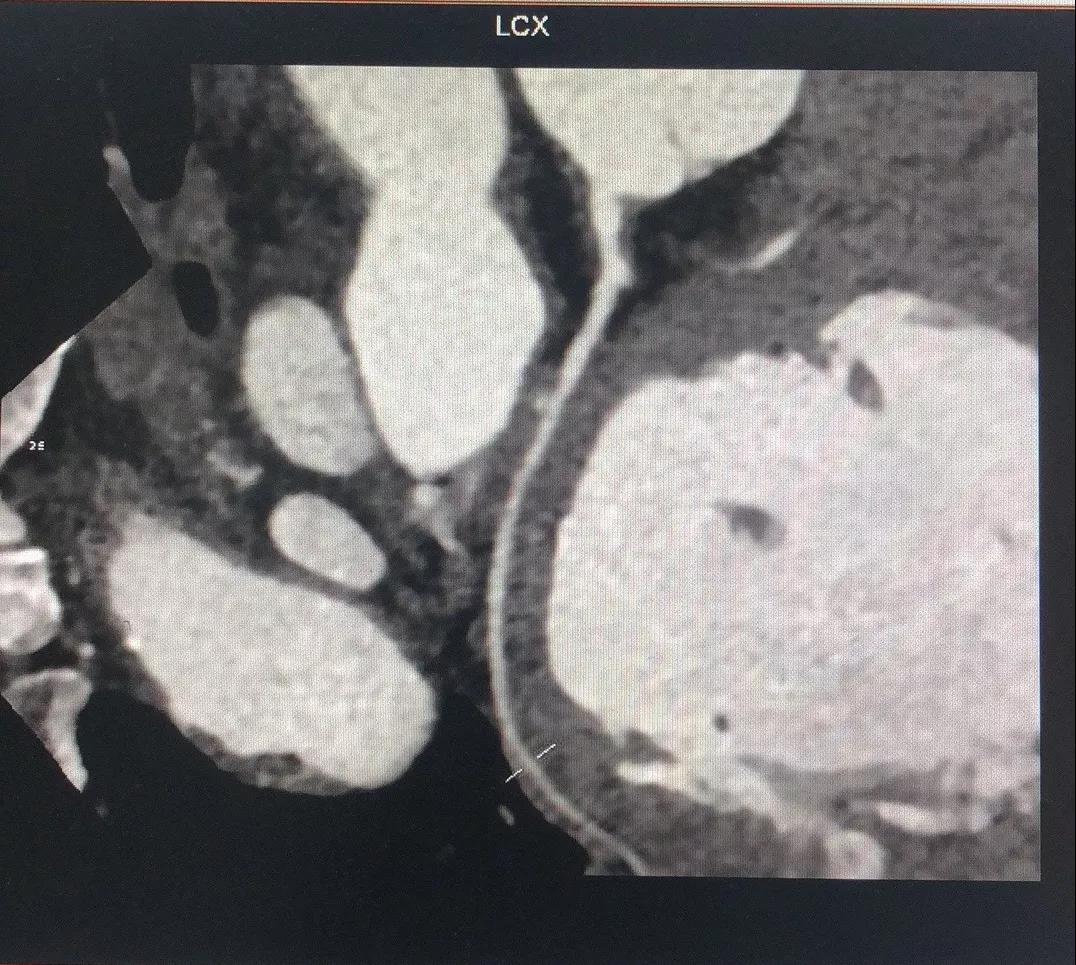

关于LCX

LCX CTA特点:

1、LCX血管相对比较“健康”;

2、LCX近中段发出比较粗大的侧枝逆向供应右冠左室后支,侧枝血管仅轻度扭曲;

3、LM前分叉相对“健康”。

有了上述信息,结合冠脉造影资料,逆向开通RCA就有了一根条件相对比较好的侧枝血管。